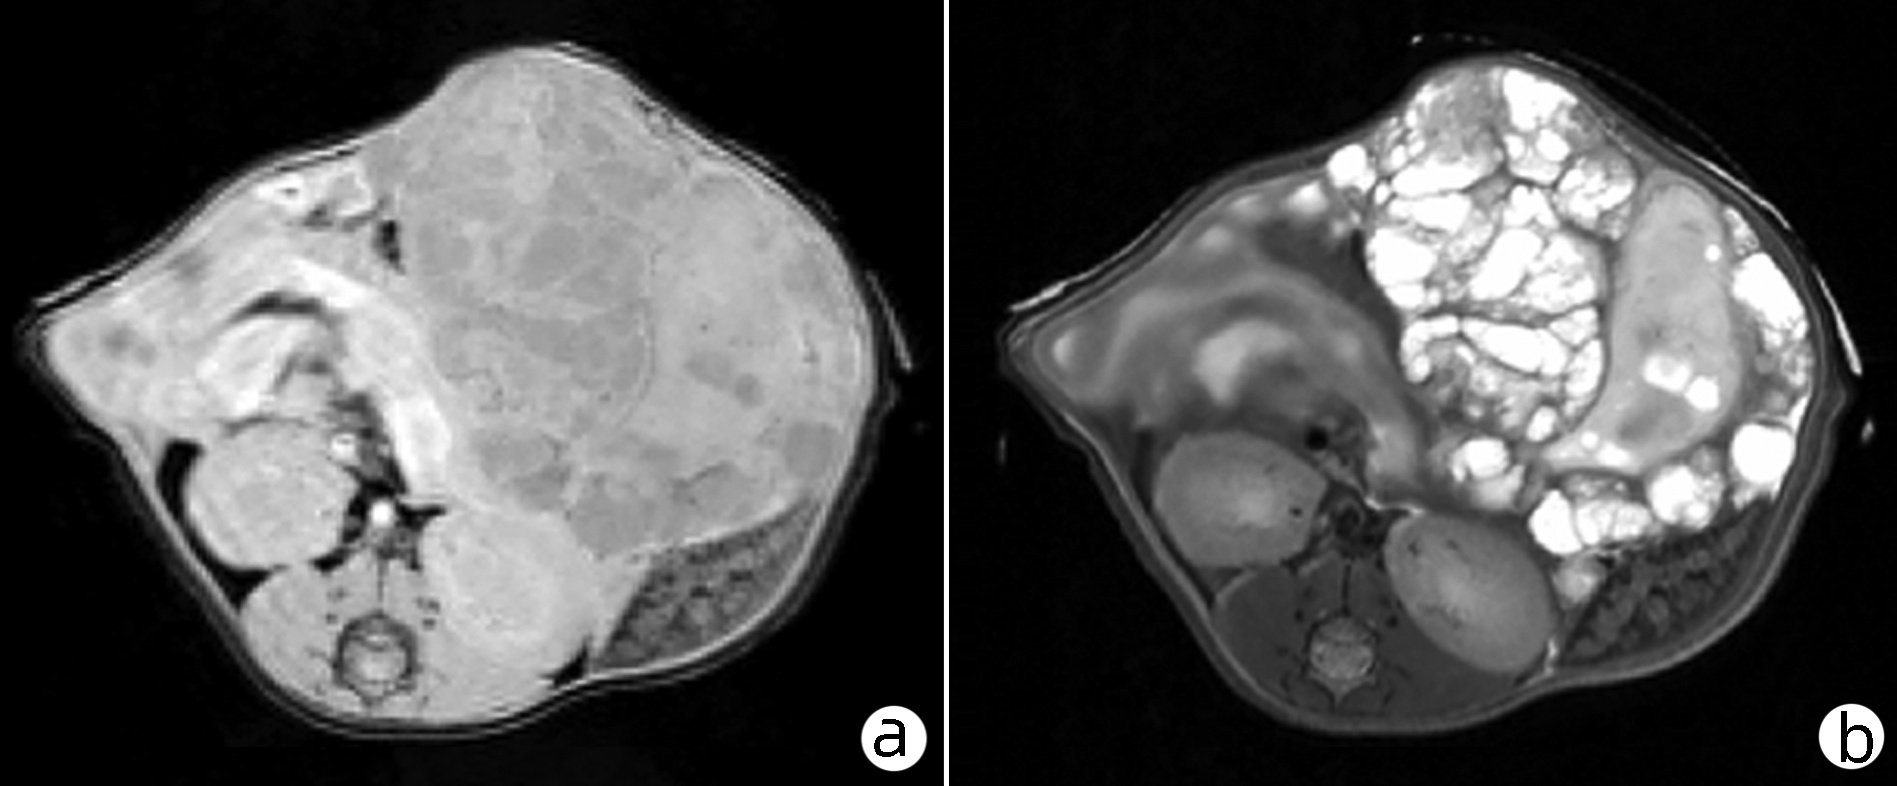

•   Objective  To investigate the effect of exosomes derived from Echinococcus multilocularis on macrophage polarization after treatment for different durations and concentrations.  Methods  A total of 60 BALB/c mice were used for modeling, among which 4 mice were selected to observe the growth of abdominal lesions on 7.0T MRI. The mice for modeling were dissected, and the protoscoleces was taken from the abdominal lesion and cultured in vitro; ultracentrifugation was used to extract the exosomes from the supernatant, and transmission electron microscopy and Western blotting were used for the characterization of exosomes. The macrophages without exosome treatment were established as control group, and the macrophages co-cultured with different concentrations of exosomes derived from Echinococcus multilocularis were established as experimental group (10 μg/mL group and 50 μg/mL group) and were cultured for 48 and 72 hours. The morphological changes of macrophages were observed under a microscope, and flow cytometry and ELISA were used to observe polarization state. A one-way analysis of variance was used for comparison of normally distributed continuous data between multiple groups, and the least significant difference t-test was used for further comparison between two groups.  Results  The results of 7.0T MRI showed the formation of diffuse lesions with different sizes in the abdominal cavity of mice, and the exosomes derived from Echinococcus multilocularis were approximately 100 nm in diameter and were cup-shaped or saucer-shaped, with the positive expression of the surface markers CD9, TSG101, and CD63. After co-culture, most of the cells in the experimental group were elongated with an irregular and polygonal shape. Flow cytometry showed that after 48 hours of co-culture, the positive rates of CD16/32, CD206, and CD369 in the control group were 99.53%±0.06%, 90.27%±0.21%, and 2.40%±0.20%, respectively; compared with the control group, except that the 10 μg/mL exosome group had a significant reduction in the positive rate of CD369 (0.80%±0.00%) (P < 0.05), all the other groups had a significant increase in the positive rates of CD16/32, CD206, and CD369 (all P < 0.000 1); after 72 hours of co-culture, the positive rates of CD16/32, CD206, and CD369 in the control group were 99.67%±0.06%, 85.47%±0.55%, and 6.60%±0.20%, respectively, and compared with the control group, the experimental group had significant increases in the positive rates of CD16/32, CD206, and CD369 (all P < 0.05). ELISA showed that after 48 hours of co-culture, the levels of IL-6 and TNFα in the control group were 58.53±15.52 pg/mL and 320.70±5.30 pg/mL, respectively, and when the exosome concentration was 50 μg/mL, the level of IL-6 in the experimental group was 98.81±15.55 pg/mL, which was higher than that in the control group (P < 0.05); after 72 hours of co-culture, the levels of IL-6 and TNFα in the control group were 76.22±9.68 pg/mL and 323.90±87.37 pg/mL, respectively, and when the exosome concentration was 10 μg/mL, the level of TNFα was 164.20±14.17 pg/mL, which was significantly lower than that in the control group (P < 0.05); when the exosome concentration was 50 μg/mL, the level of IL-6 was 99.52±8.35 pg/mL, which was significantly higher than that in the control group (P < 0.05).  Conclusion  Exosomes derived from Echinococcus multilocularis can regulate macrophage polarization and induce M2-like polarization of macrophages after co-culture at a concentration of 10 μg /mL for 72 hours, and further studies are needed to clarify the specific method.